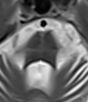

51.59歲男性因為姿勢性低血壓暈倒多次,他同時還有動作遲緩、步態不穩及性功能障礙問題,他的腦部磁振造 影掃描結果如下圖,下列何者為最可能的診斷?

(A)行為變異型額顳葉失智症(behavioral variant frontotemporal dementia)

(B)阿茲海默氏病(Alzheimer disease)

(C)多重系統萎縮症(multiple system atrophy)

(D)進行性上眼神經核麻痺症(progressive supranuclear palsy)